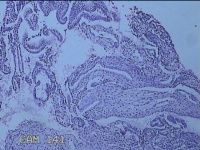

宫腔内容物

性别

女

年龄

47岁

临床诊断

1.异常子宫出血 2.慢性宫颈炎

一般病史

不规则阴道流血21天。

标本名称

大体所见

灰白暗红色不规则碎组织2.5x1.8x0.3cm一堆。

图3